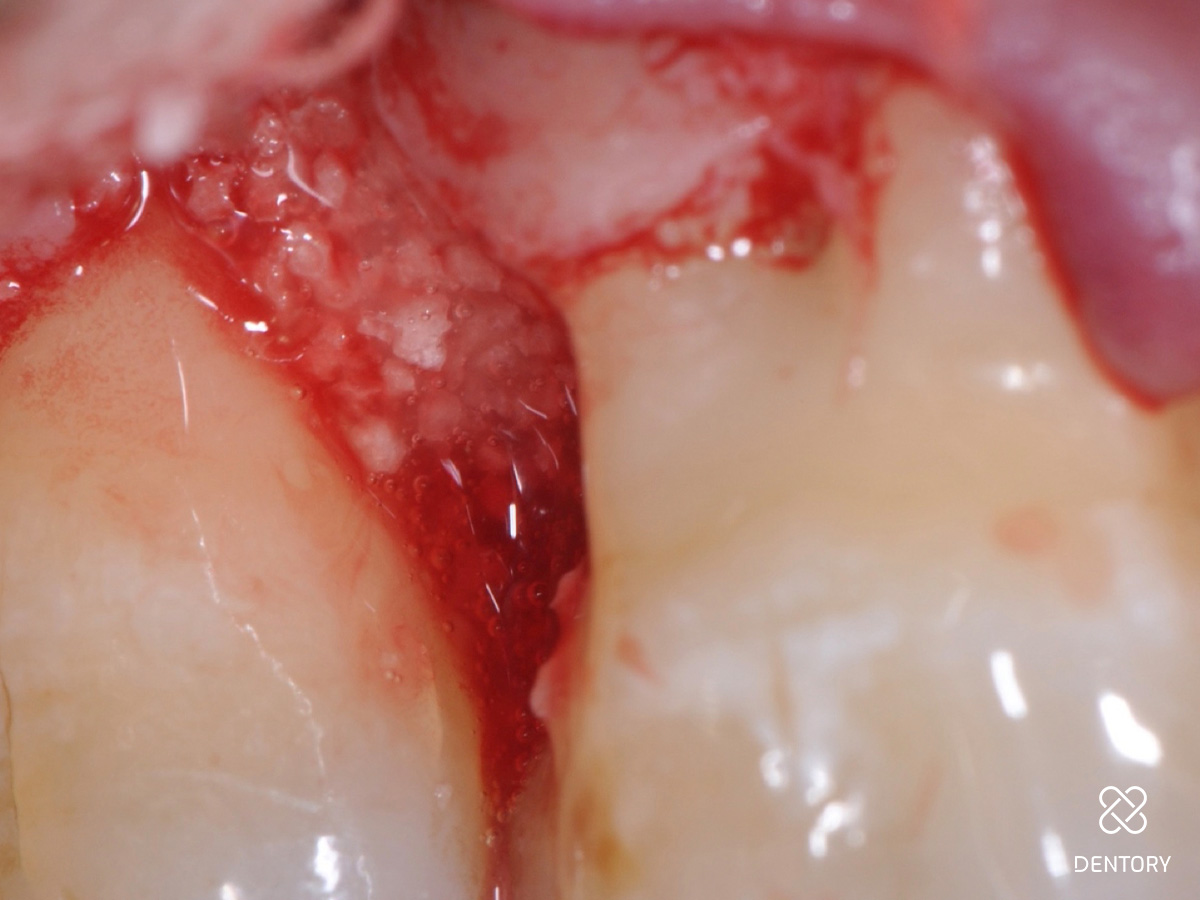

Abbildung 7

Darstellung des knöchernen Defektes. Es handelt sich um einen zweiwandigen knöchernen Defekt. Hier empfiehlt sich die kombinierte Anwendung von Schmelz-Matrix-Proteinen mit einem Knochenersatzmaterial. Das Knochenersatzmaterial verhindert ein Kollabieren bzw. Zusammenfallen des Weichgewebes in den Defekt.